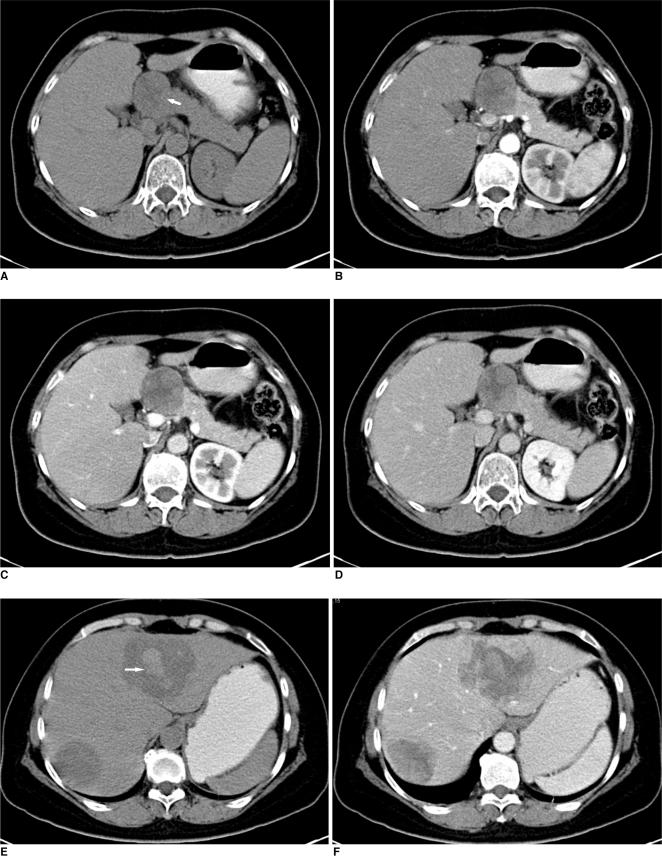

Extragonadal yolk sac tumor (YST) is a relatively rare entity. We describe here the case of an extragonadal YST that occurred in the pancreas with hepatic metastasis in an adult woman. The contrast enhanced CT images of the abdomen revealed a heterogeneous, solitary mass occupying the pancreatic neck and body with slightly inhomogeneous contrast enhancement. Two low-density lesions in the liver were also displayed on the CT images. The patient underwent surgery and the diagnosis of YST was pathologically verified.